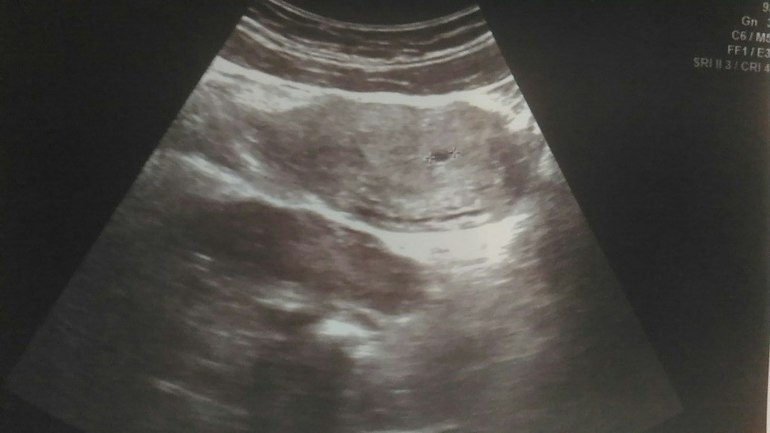

Итак, были вчера на узи. Увидели все там, где надо! А для нас после внематочной это счастье) Да еще и ПЯ не маленькое - 6.3 мм, хотя задержка всего 5 дней была) Дальше под кат.

В общем сказали все нормально, эндик хороший, ЖТ соответствует, и т.д. Но ПЯ деформировано. Врач вроде норм, сказала, что скорее всего просто из-за срока и все выровняется. Предложила утрожестан ставить до следующего контроля через 10-14 дней, но это на наш выбор и не обязательно. Как вы считаете? С прогестероном вроде проблем не было никогда, да и про деформацию сколько не читала, вроде как на этом сроке не критично.

Снимки:

Абдоминально